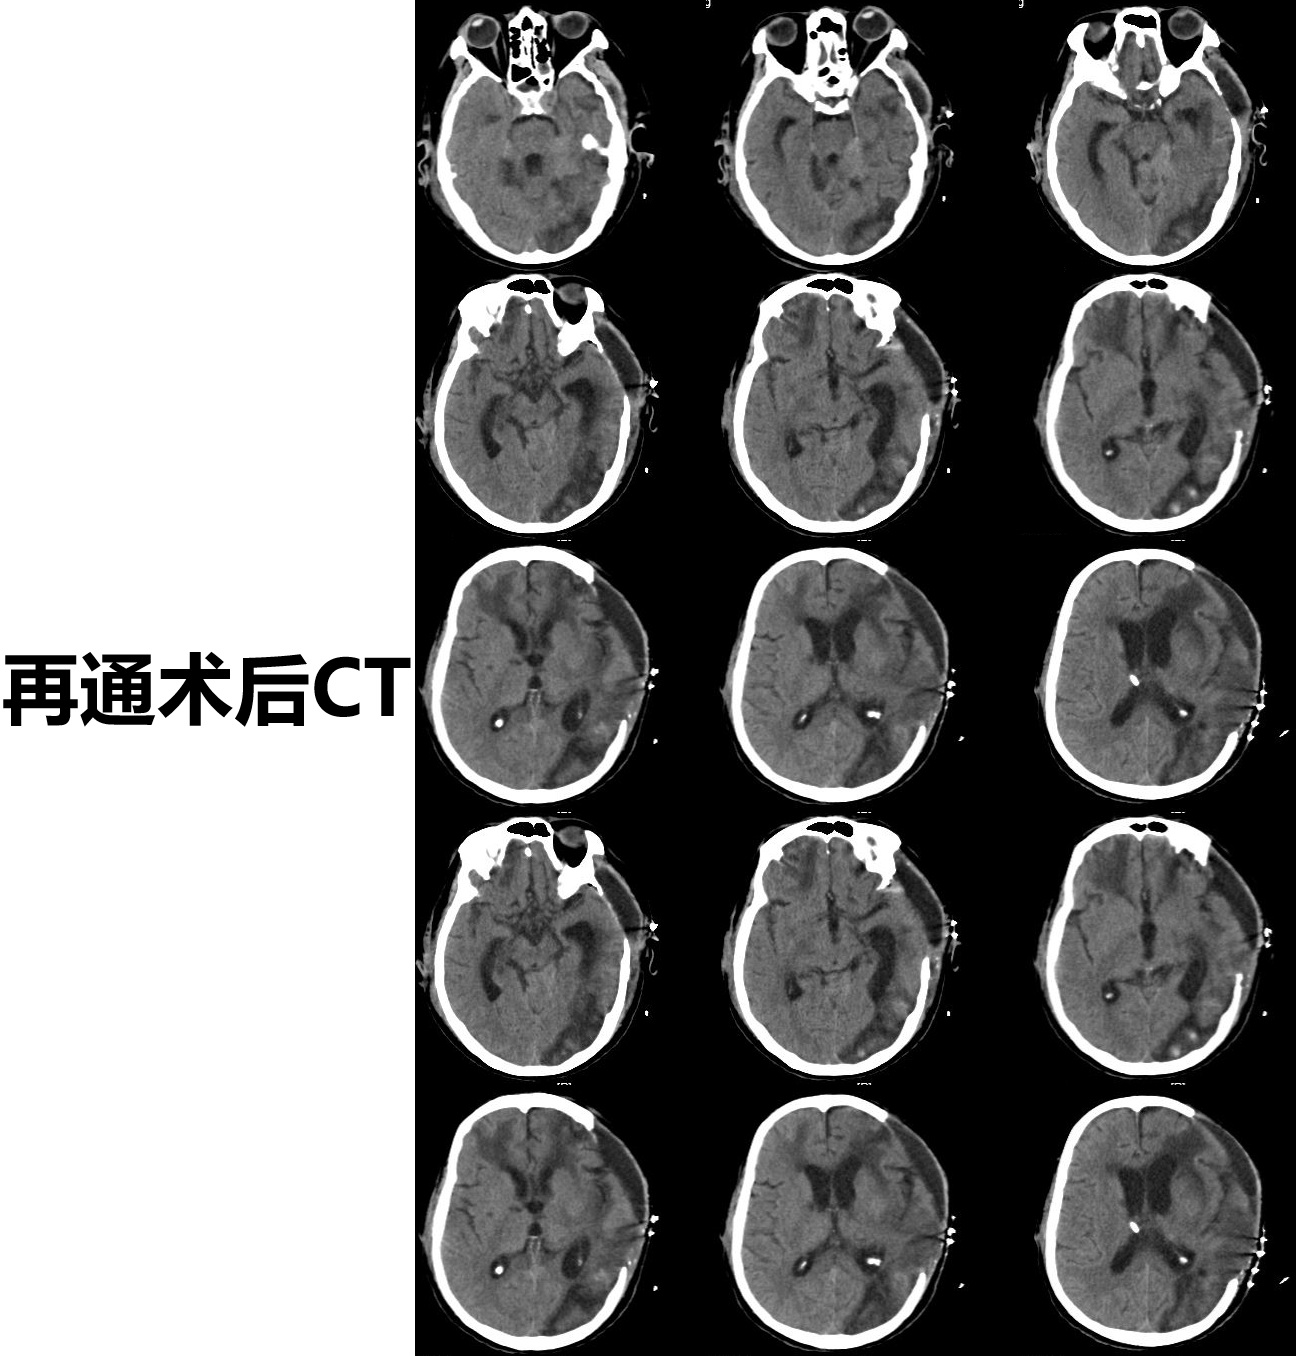

患者为机器碾压导致的复合伤,考虑外伤诱发左侧颈总动脉闭塞,导致多发脑梗死,予以去骨瓣减压手术,病情平稳后,查DSA提示:左侧颈总动脉闭塞,闭塞段位于颈2椎体至颈6椎体之间。和家属充分沟通后,行显微左侧颈动脉开通手术,手术顺利,术后患者症状明显好转,特此分享。